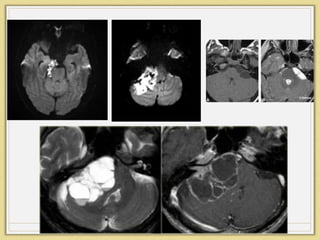

Epidermoid

• Imaging

• XR

• Scalloped margins

• MRI

• T1-hypointense

• T2-hyperintense

• Some tumors show rim enhancement

• Restricted diffusion on DWI as a result of restriction of

water movement

• CT

• Bone erosion is seen in 30%